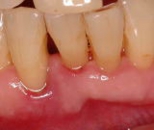

タバコを吸うとどうして悪いの?

タバコに含まれているニコチンという物質には、血管を収縮させる作用があります。そのため、血管が膨張して見られる発赤、腫脹が現れにくく、気付かないうちに進行していることが多いのです。

また、タールという物質が歯に付着してしまうと、歯面がざらついてしまいます。一般的に「ヤニ」と呼ばれているものですが、ざらついている歯面は、プラーク(細菌の塊)を付着しやすくさせます。

要するに、喫煙者は、ヤニの付着によりざらつく歯面になるため、プラーク(細菌の塊)がたまりやすく、抵抗力が弱まることにより非喫煙者と比較すると歯周病の進行が早く進んでしまいます。(1日1箱で約4.72倍)にもかかわらず、ニコチンにより目で見える発赤、腫脹が現れにくく、気づかぬうちにかなり歯周病が進んでいることが多いのです。ですので、喫煙者の方は、定期的に歯科医院を受診し、歯周病の進行をチェックしていく必要があります。